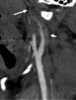

Vascular injury

A gunshot wound (GSW) is physical trauma caused by a bullet from a firearm. Damage may include bleeding, broken bones, organ damage, infection of the wound, or loss of the ability to move part of the body. [Source: Wikipedia ]